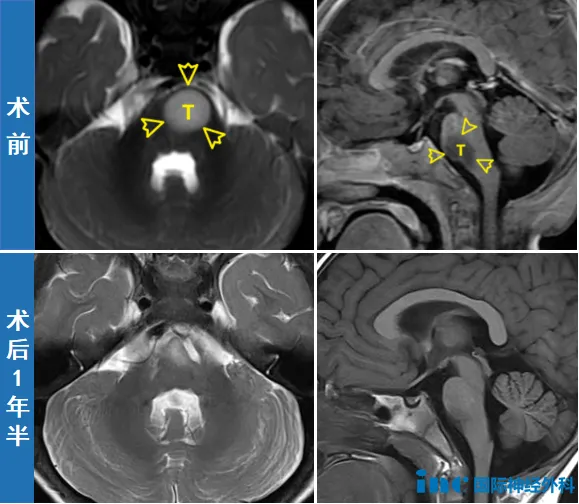

两个月后,11个月大的新新成为巴教授示范手术中年龄最小的患者,但手术难度远超其他病例。位于脑干关键区域的肿瘤、与神经纤维的危险解剖关系、仅10kg的体重、极低血容量和耐失血能力、高休克与麻醉风险……所有这些因素都让钟女士全家心情紧张。

实际上,新新的手术除了因年龄小、体重轻导致的血液总量少、耐失血能力弱、麻醉和休克风险高之外,还存在肿瘤位置特殊带来的额外风险——由于肿瘤位于脑干,且与神经及运动纤维关系紧密,术中存在心跳骤停可能,或因损伤第六颅神经及运动纤维而产生并发症。

手术很快开始。尽管术中巴教授发现肿瘤与周围正常组织边界极其模糊,几乎无法分辨,但凭借教授数十年熟练操作经验和先进设备保障,最终手术顺利,实现满意切除,未损伤患儿神经功能。

现在,新新已顺利长大,2岁的他依然活泼,手举旗子跳舞。巴教授看到后非常欣慰:"(他)看起来非常好,确实很不错。他还那么小,而且非常活跃,发育状况已经很良好。"

接下来一年,新新只需定期复查,钟女士一家也重回正常生活。陪伴新新平安成长,成为全家最大的快乐和愿望。